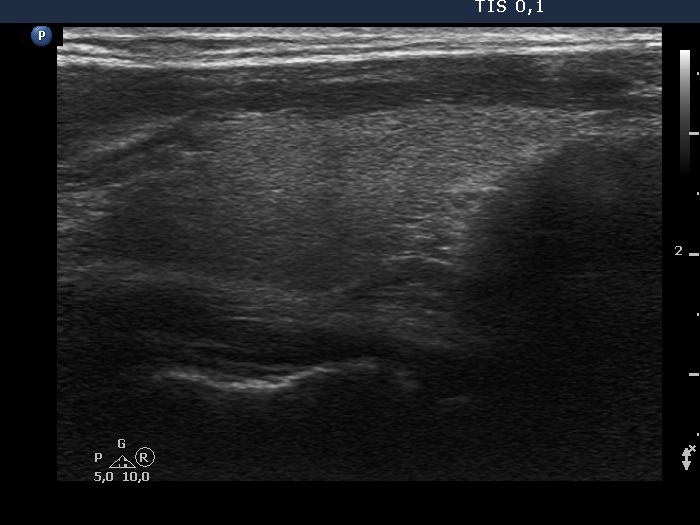

Study on 100 consecutive patients with thyroid nodule - case 023

One year before the present examination (ultrasonographic picture 7)

Left lobe, longitudinal scan.